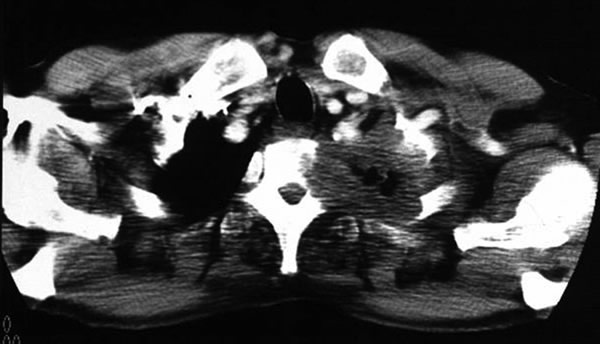

The subclavian artery can usually be dissected through the subadventitial plane (Video 8). Local branches (e.g., the internal mammary artery, thyrocervical trunk, or occasionally the vertebral artery) should be identified and transected if necessary. If the subclavian artery is invaded by tumor (Figure 10), the involved segment can also be resected and reconstructed through a posterior approach (Figure 11). After systemic heparinization, the artery is cross-clamped proximally and distally excluding the invaded segment and revascularized using either an end-to-end anastomosis or, more commonly, the interposition of a polytetrafluoroethylene (PTFE) graft, 6 to 8 mm in diameter (Video 9).

| Figure 10. Chest CT-scan shows the invasion of the subclavian artery by Pancoast tumor. | Figure 11. The invaded artery was resected and replaced by a PTFE graft through a posterior approach. |